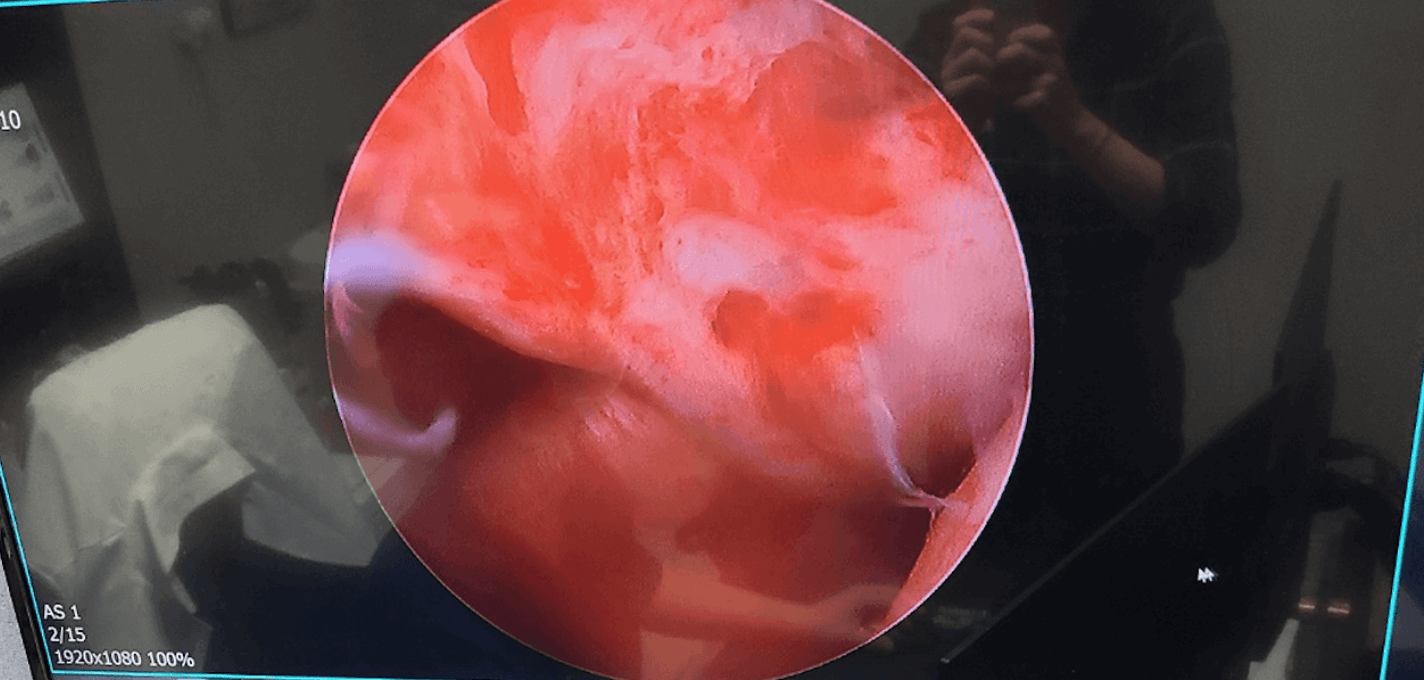

어깨충돌증후군 수술

이러한 어깨충돌증후군 증상이 있는 것을 치료하지 않아 방치할 경우 회전근개 파열로 이어지고 이것이 오래되면 어깨를 영구적으로 움직일 수 없게 될 수도 있습니다.

회전근개 파열 크기와 파열된 기간에 따라 회복방법은 달라지며, 부분파열로 범위가 작을수록 수술 회복속도가 빨라집니다. 보통 수술 후 1년 정도 회복기간이 소요됩니다.